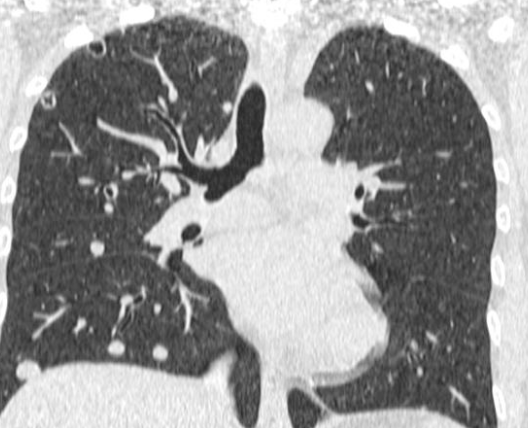

Lacher de Ballon

- Carcinome Rénal ++

Cannonball en anglais

Distribution vasculaire = Prédominent aux plages inf.

Distribution vasculaire = Prédominent aux plages inf.